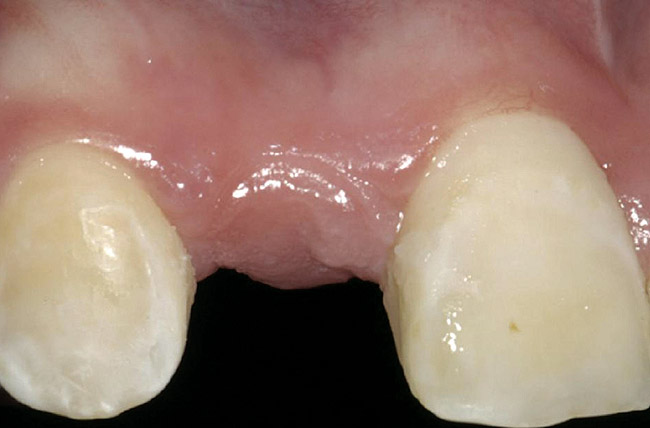

Figure 2  Congenitally missing maxillary right lateral incisor.

Figure 2

A 16-year-old female patient with a congenitally missing maxillary right lateral incisor was referred for an implant-supported crown. Clinical and CBCT evaluation revealed both a facial and palatal bony width deficiency (Figure 2 and Figure 3). The treatment plan included the use of titanium mesh and rhBMP-2/ACS (INFUSE® Bone Graft) along with mineralized allograft (MinerOss®, BioHorizons, www.BioHorizons.com) for bony augmentation (Figure 4 and Figure 5). After 7 months, the graft was found to be well incorporated and allowed for placement of a 3.8-mm x 10.5-mm diameter root form implant that was restored 3 months later (Figure 6, Figure 7, Figure 8, Figure 9 and Figure 10).

Figure 6  Facial and palatal alveolar ridge width deficiency.

Figure 6